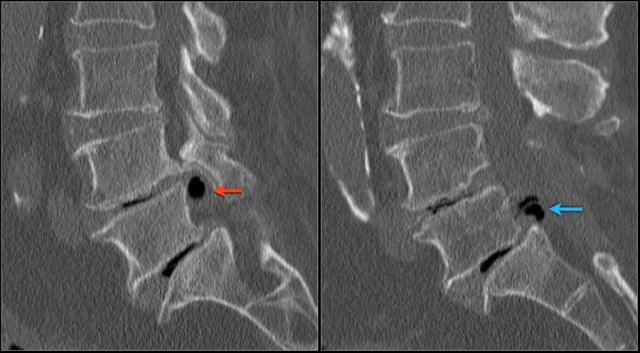

The low signal intensity could finally be explained by the vacuum phenomena due to nitrogen gas within the herniated disc both on L4L5 (red arrow) and L5S1 level (blue arrow)